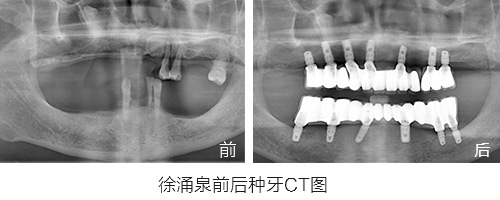

种植情况:全口种植

徐先生的种牙笔记:记录一年多的种牙经历